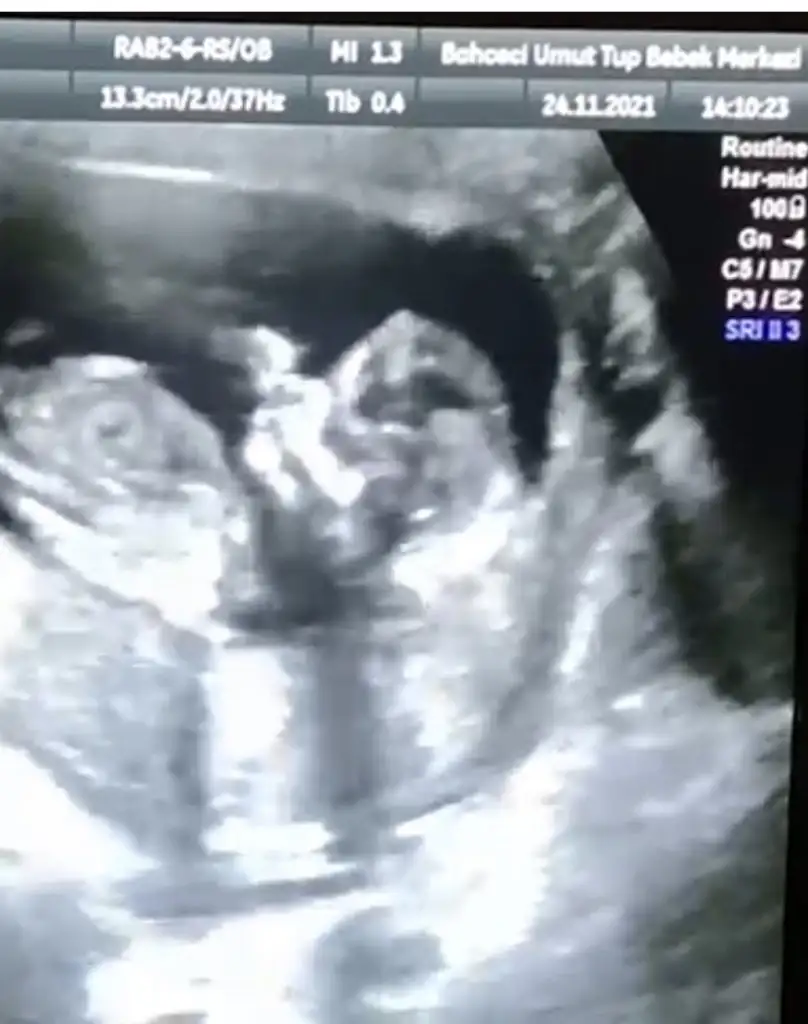

ahanda bir yerinde durmayan kuduruk bebek daha. zıp zıptı benimki de :) dans ediyor gibiydi. doktor sana cinsiyet için ne demişti kuzuBugün gittim doktora ense kalınlığı falan gayet güzel dedi. Ama ben şok bebek bildiğin kuduruyordu. Ayaklarıyla ittirip zıplıyordu muayene boyunca. Doktor zor baktı. Aşırı hareketli dediDedim kuduruk olacak

Yaaa maşallah, günün ikinci zıp zıpı.Bugün gittim doktora ense kalınlığı falan gayet güzel dedi. Ama ben şok bebek bildiğin kuduruyordu. Ayaklarıyla ittirip zıplıyordu muayene boyunca. Doktor zor baktı. Aşırı hareketli dediDedim kuduruk olacak

Abooovvvv hemde nee kudurukkk görüyonmu zıplıyorr bideBugün gittim doktora ense kalınlığı falan gayet güzel dedi. Ama ben şok bebek bildiğin kuduruyordu. Ayaklarıyla ittirip zıplıyordu muayene boyunca. Doktor zor baktı. Aşırı hareketli dediDedim kuduruk olacak

Erkeğe benziyor dedi. Ay valla doktor baya çabaladı bakmak için çünkü öyle böyle değilevet bebişi görmek çok iyi geldi. afacan öyle zıplıyordu ki dans ediyor gibi hiç durmadı yerinde hahaha